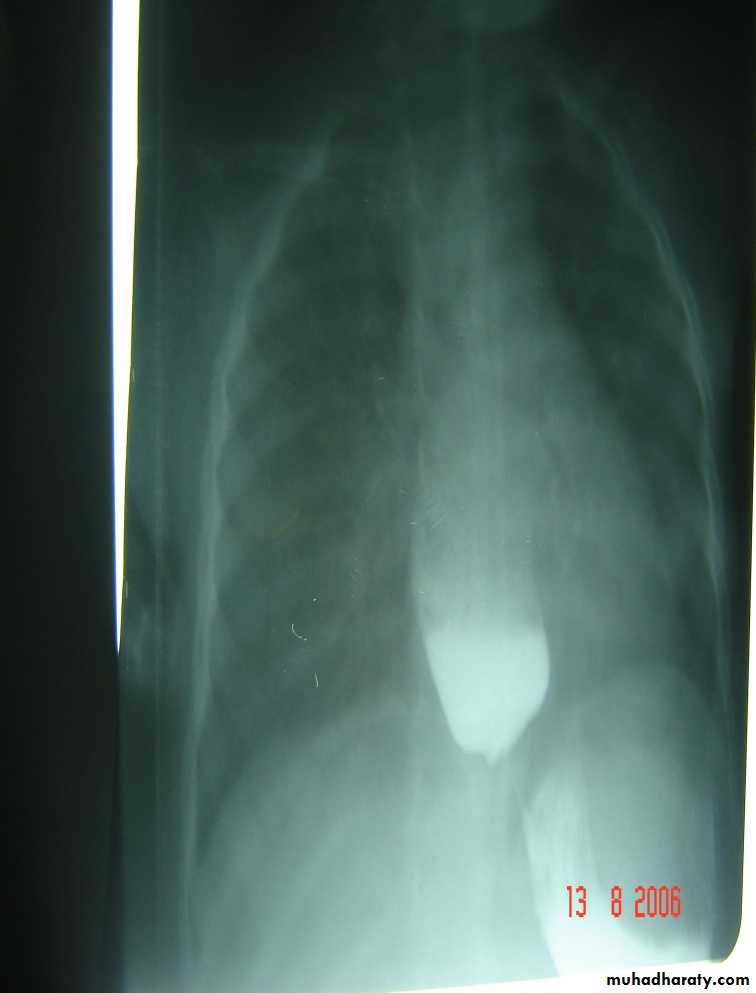

Diagnosis: pyloric stenosis(IHPS infantile hypertrophic pyloric stenosis—this name should be mentioned)

• Ba-meal dilated stomach – failure to pass to intestine – string sign

surgery pyloromyotomy (rami stick surgery)Diagnosis: achalasia cardia

Ba-swallow dilatation of esophagus with narrowing of lower part.